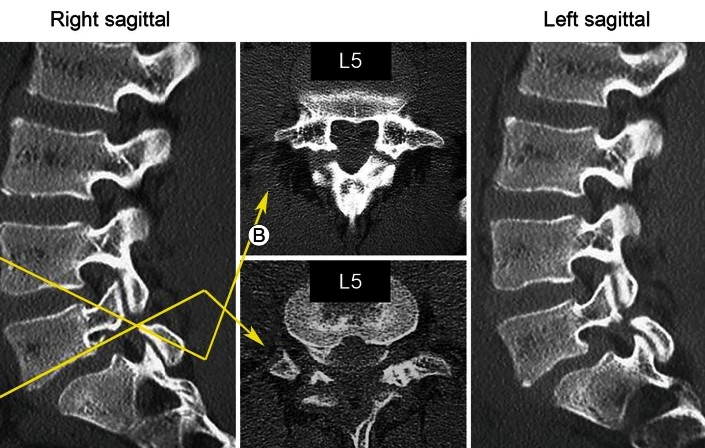

척추분리증은 척추의 일부가 분리되거나 약해지는 상태를 말합니다. 이 조건은 보통 척추의 추궁의 특정부분이 결손되거나 분리되는 데 관련되며, 이는 척추를 안정시키는 데 중요한 구조물입니다. 이것은 가장 흔하게는 척추의 하부인 요추 부분에서 발생합니다.